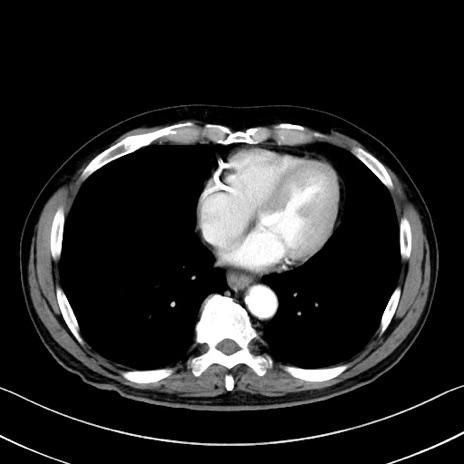

症例35(横断像)

【症例】70歳代 男性

【主訴】腹部膨満、嘔吐

【現病歴】昨日より腹部膨満感出現。本日増悪し、仙痛出現。嘔吐あり、受診。

【既往歴】糖尿病、胆摘後

【身体所見】BP 149/80mmHg、HR 74/min、BT 35.9℃、腹部:膨満、軟、圧痛なし。腸雑音減弱あり。上腹部正中切開瘢痕あり。

【データ】WBC 13500、CRP 1.72